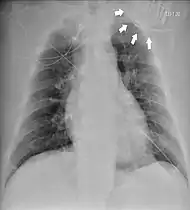

Chest radiograph showing twiddler's syndrome. The leads of the automated external defibrillator are wrapped around the device and can't be seen in the ventricle. | |

Twiddler's syndrome is a malfunction of a pacemaker due to manipulation of the device and the consequent dislodging of the leads from their intended location. As the leads move, they stop pacing the heart and can cause strange symptoms such as phrenic nerve stimulation resulting in abdominal pulsing or brachial plexus stimulation resulting in rhythmic arm twitching.[1] Twiddler's syndrome in patients with an implanted defibrilator may lead to inadequate, painful defibrillation-shocks.[2]